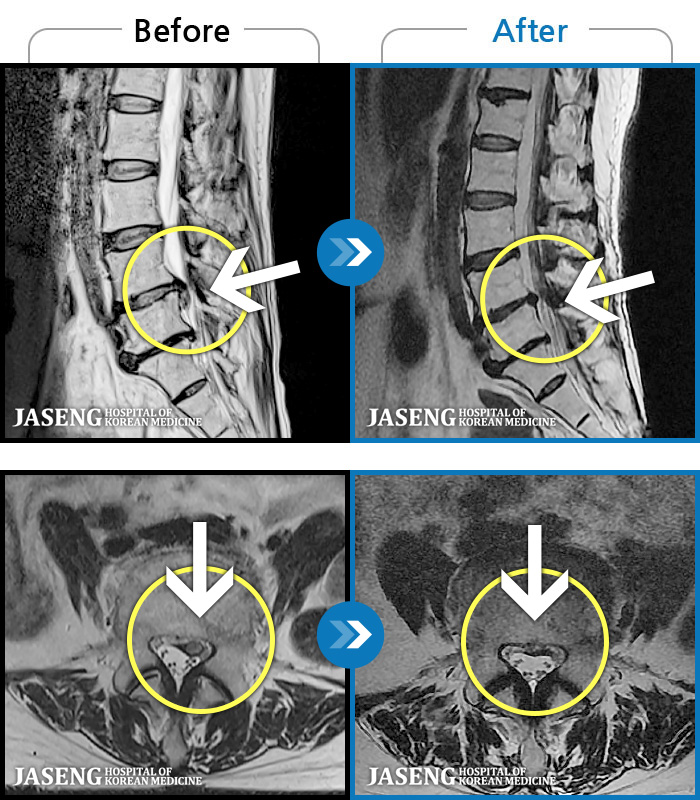

- MRI ġ

MRI ġ

MRI ũ ʸ Ȯϼ.

Ƹ ϰ ־.